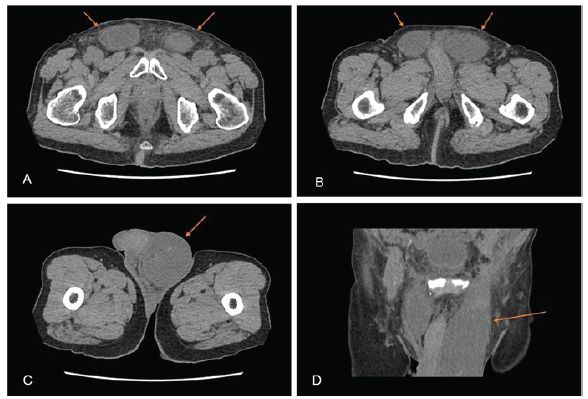

术后两周,患者于门诊就诊,诉左阴囊肿大,右腹股沟区域肿大略小。经超声(US)和骨盆CT检查均未发现疝气复发。然而,从腹股沟上内侧到左半阴囊有一13x5x6cm的血肿聚集,右腹股沟区域有7x3x4cm的血肿聚集(图1)。可能由于血肿的重量和体积较大,患者站立时出现疼痛,且无法保持舒适坐姿。患者最终同意手术清除血肿。

图1 CT扫描图像(A-C轴位、D冠状位)显示从腹股沟上内侧向左半阴囊延伸的血肿,大小为13x5x6 cm;右腹股沟区域血肿,大小为7x3x4 cm (箭头所指为血肿)